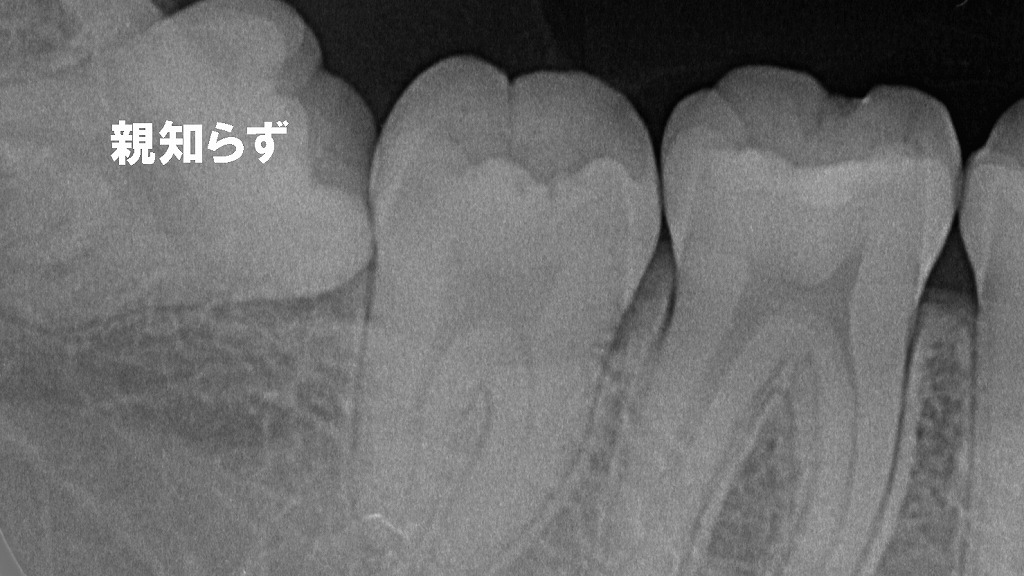

③ 萌出による圧迫

この画像は、上顎の小臼歯(主に第二小臼歯)が萌出し始めている状態を示しています。

赤い矢印の位置を見ると、歯ぐきの下から歯の頭が少し透けて見え、周囲の粘膜がほんのり盛り上がっています。これは永久歯が歯ぐきを押し上げているサインです。

✔ 歯がムズムズ・むずがゆい理由

歯が生えてくるとき、

- 歯ぐきの内側で歯が押し上げる圧力

- 隣の歯に当たり始める接触刺激

- 歯ぐきの軽い炎症

などが起こり、それが 「ムズムズする」「気になる」「触りたくなる」 といった感覚につながります。

特に小臼歯は、交換期になると上下で順番に生えてくるため、周囲に違和感が出やすい部位です。

✔ 痛みが強くないのが特徴

萌出時のムズムズ感は、

- 触ると少し気になる程度

- 軽い圧迫感

- 噛むと違和感がある

といった症状が多く、強い痛みではないことが一般的です。

✔ 放置しても基本的には問題なし

歯の萌出によるムズムズ感は、一時的なもので、歯がしっかり生えてくると自然に消えていきます。

ただし、

- 痛みが強い

- 腫れが続く

- 歯ぐきが白く膿んでいる

といった場合は、別の問題(感染・萌出スペース不足など)が隠れている可能性があります。